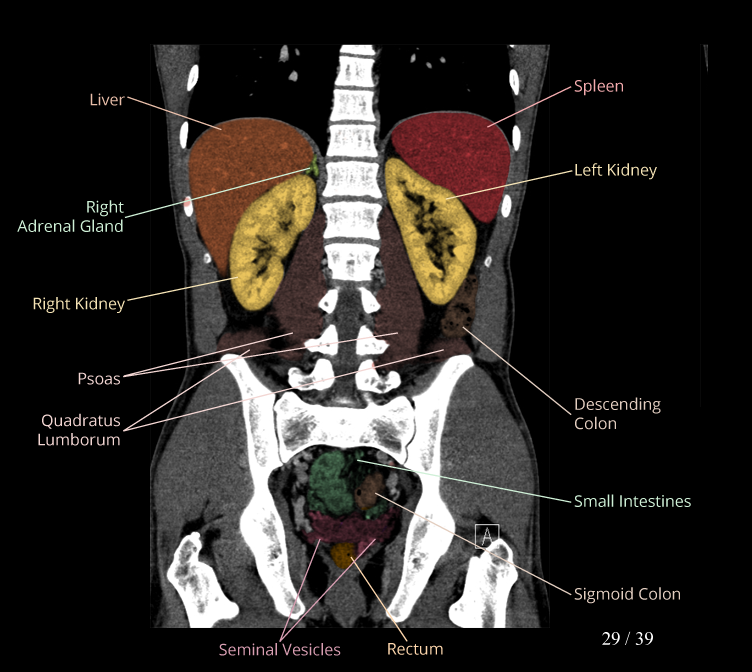

Body

Covers abdominal CT anatomy.